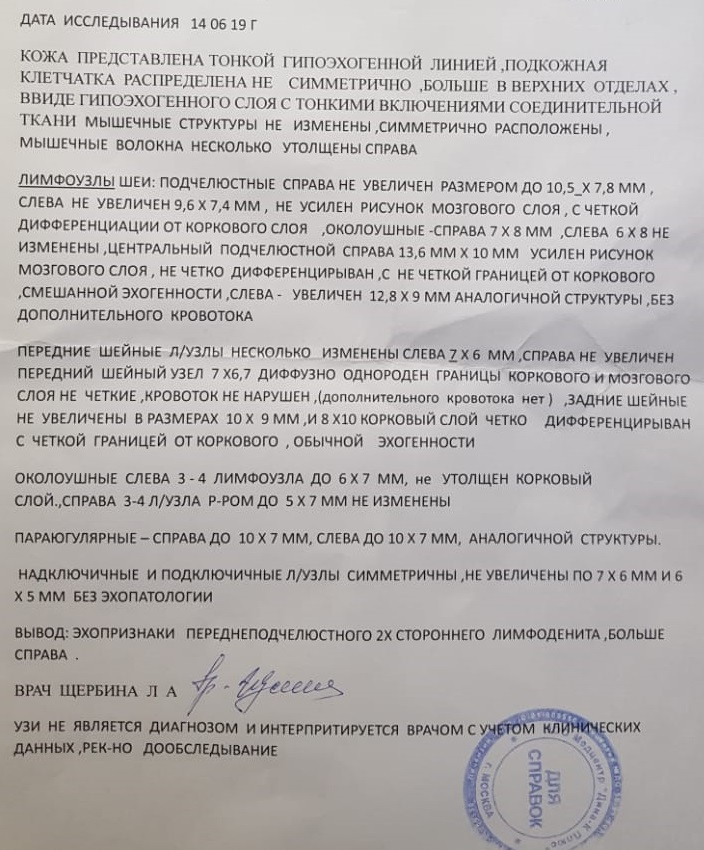

Мезентериальные лимфатические узлы: УЗИ и диагностика

Раздел: Лаборатория идей